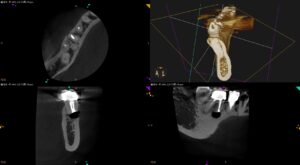

根尖病変掻爬のタイミングは, もしそれをするなら, Root resectionの次の段階であるという根拠は?〜#30 M Apicoectomy

紹介先の患者さんの治療。 主訴は、 右下奥歯、被せた歯が腫れた… である。 ⭐︎この後、検査動画が出てきます。不快感を感じる方は視聴をSkipしてください。 歯内療法学的検査(2024.12.5) 患歯はSinus tr … 続きを読む 根尖病変掻爬のタイミングは, もしそれをするなら, Root resectionの次の段階であるという根拠は?〜#30 M Apicoectomy